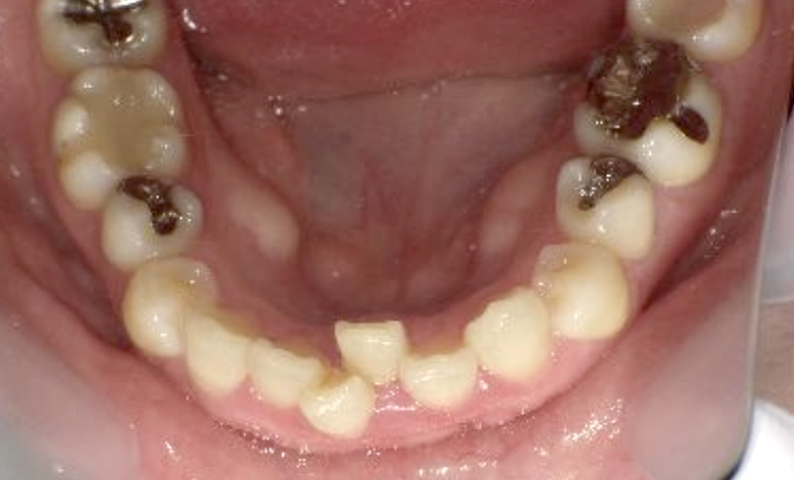

症例_003 下顎だけの部分矯正

治療期間:10ヶ月金額:24万円+税女性前歯のガタガタ下の前歯だけ上顎は補綴治療中

| Before | After |